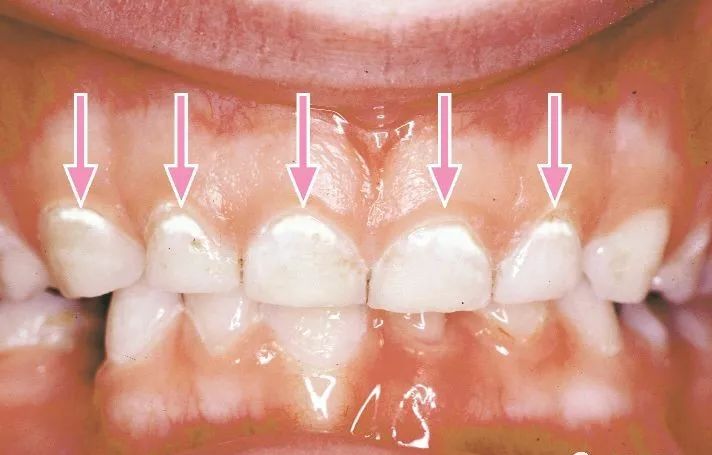

A图:重度蛀牙

B图:靠近牙龈的地方有白色斑块,是蛀牙早期表现,说明牙齿开始慢慢脱框

C图:食物残渣长期聚集在两个牙齿之间,没有刷干净而产生的灰色龋块

D图:牙面上有黑色斑点,称之为龋块

以上都是龋齿不同程度所表现出来的状态,所以要养成定期去医院检查的好习惯。